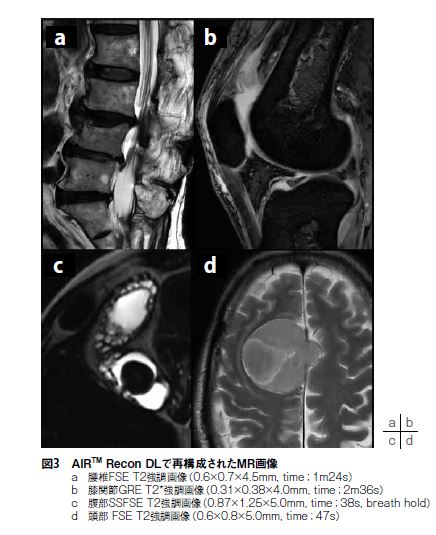

AIR™ Recon DLは現在2Dのみの対応ではあるが、spin echo(SE)系、gradient echo(GRE)系、diffusion weighted image(DWI)、FIESTA、single-shot fast spin echo(SSFSE)の幅広いコントラスト・撮像法に対応している。当院の運用として、AIRTM ReconDLによってSNRに余裕が生まれるため、最短echo spaceになるよう受信バンド幅を調整しつつ、収集ボクセルサイズを検査全体で平均約35%向上させた。さらにAIR™ Recon DL自体にも鮮鋭度を向上させる効果(従来再構成よりも約30%鮮鋭度が向上)があるため、視覚的インパクトは想像以上である(図3)。体動やフローアーチファクトの影響無ければ、加算回数(NEX)を積極的に減らすことができるため、撮像時間の短縮に繋がる。急に画質が良くなりすぎると逆に違和感を持つ人もいるかもしれないが、AIR™ Recon DLはdenoisinglevelを3段階調整可能なため、適度にノイズがのった鮮鋭度の高い画像を得ることもできる。